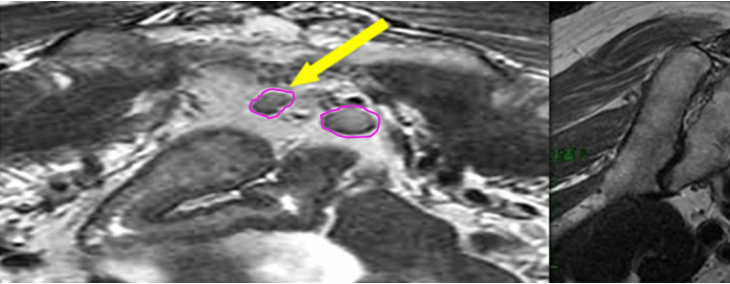

a) GTV(紅色)通過對比定位 MR 圖像,在 CT 定位圖像完成 GTV 的勾畫(圖 1)。

圖 1 直腸癌 GTV 勾畫示例

b) GTVnd(粉色) :轉移淋巴結在診斷磁共振或定位磁共振圖像顯示清楚,可參考并輔助在 CT 定位圖像完成 GTVnd 的勾畫(圖 2-圖 4)。